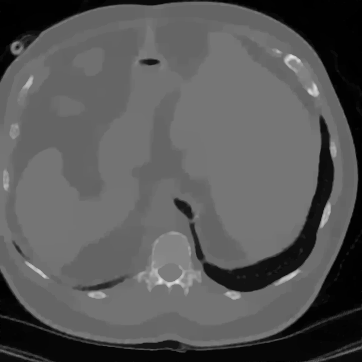

In Figure 12 we compare the PD3O reconstructions (top) and their corresponding errors with respect to the ground truth (bottom) using different regularization parameter choices , and for PD3O. Obviously, using the estimated parameter-map leads to a significant improvement of the reconstruction. In particular, sharp edges are retained, while using a constant regularizing parameter results in a significant blur. This can be also seen in Table 4, where we compare the NRMSE, PSNR, SSIM and blur and evaluated on the first 100 test images of the LoDoBaP dataset. These results are visualized in Figure 13 using box-plots. Note that the FBP seems to better than PD3O- in terms of the blur effect, but this can be explained by the fact that FBP reconstructions admit a lot of high-frequency artefacts leading to a small blur effect.

Further PD3O- reconstructions with their corresponding estimated parameter-maps are shown in Figure 14. Note that the parameter-maps are given in a logarithmic scale. As expected, the regularization is strong in constant areas and less strong on edges or finer details in order to reduce a smoothing in these regions.